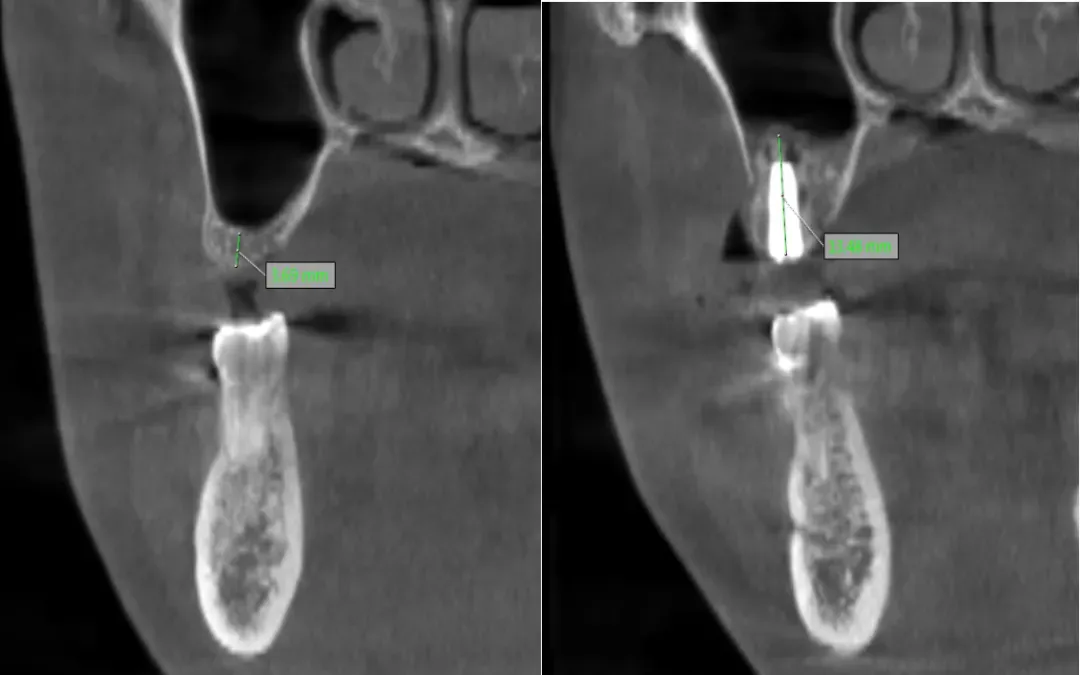

種植牙成功的核心在于充足的骨量支撐,對(duì)于骨量嚴(yán)重不足的患者,術(shù)前精準(zhǔn)評(píng)估與科學(xué)規(guī)劃非常重要。延安市中醫(yī)醫(yī)院口腔科閆慧鑫主任帶領(lǐng)團(tuán)隊(duì),結(jié)合患者全身健康狀況、口腔功能需求及美學(xué)期待,運(yùn)用三維CBCT影像技術(shù)對(duì)頜骨進(jìn)行全方位、立體化掃描分析。通過(guò)精準(zhǔn)測(cè)量剩余牙槽骨的高度、寬度,明確上頜竇位置與形態(tài),同時(shí)模擬手術(shù)全過(guò)程與修復(fù)效果,最終為患者制定了上頜竇外提升同期種植體植入的個(gè)性化手術(shù)方案,讓每一份骨量都能得到充分利用。

術(shù)前骨高度? ? ? ? ? ??術(shù)后骨高度及種植體

手術(shù)中,閆慧鑫主任帶領(lǐng)團(tuán)隊(duì)將數(shù)字化導(dǎo)航技術(shù)、微創(chuàng)理念與精準(zhǔn)外科操作深度融合,在確保上頜竇開(kāi)窗完整、黏膜剝離無(wú)損的前提下,小心翼翼分離并提升上頜竇黏膜,再精準(zhǔn)植入骨材料以增加骨高度,為種植體植入創(chuàng)造理想條件,隨后順利完成了骨材料植入與種植體植入。